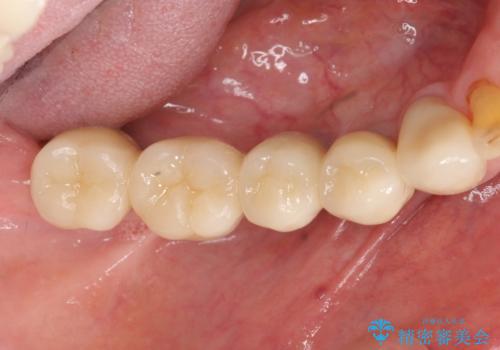

奥歯のインプラント治療

- 奥歯を失い噛めない、しっかりと噛めるようになりたいと希望され来院されました。

清掃性に優れたジルコニアカスタムアバットメント、ジルコニアクラウンを用いて機能性だけでなく審美性・予知性を高めます。

- 130万円(HAインプラント×3・骨造成・ジルコニアカスタムアバットメント×3・ジルコニアクラウン×4)費用は治療当時の料金となります